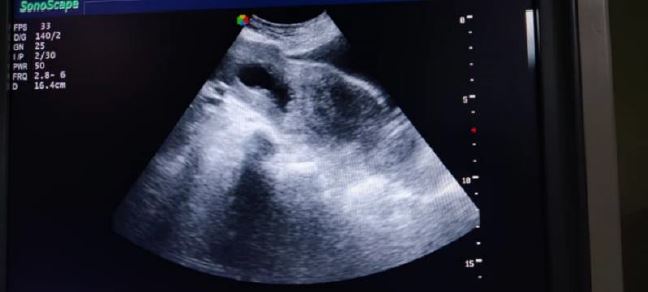

Fig 4 A third case described: VUS I* cervical canal, partially dilated by the pregnancy in the upper part, with the pregnancy extending towards the bladder type 2 CSP.

Fig. 4 B third case described: Saline Infused Sonography (SIS) Abdominal US with filled bladder. The uterine cavity is clearly seen at the right-hand side of the picture with in the lower part of the image the pregnancy extending towards the bladder no residual tissue can be made out between bladder and CSP (Type 2 CSP).